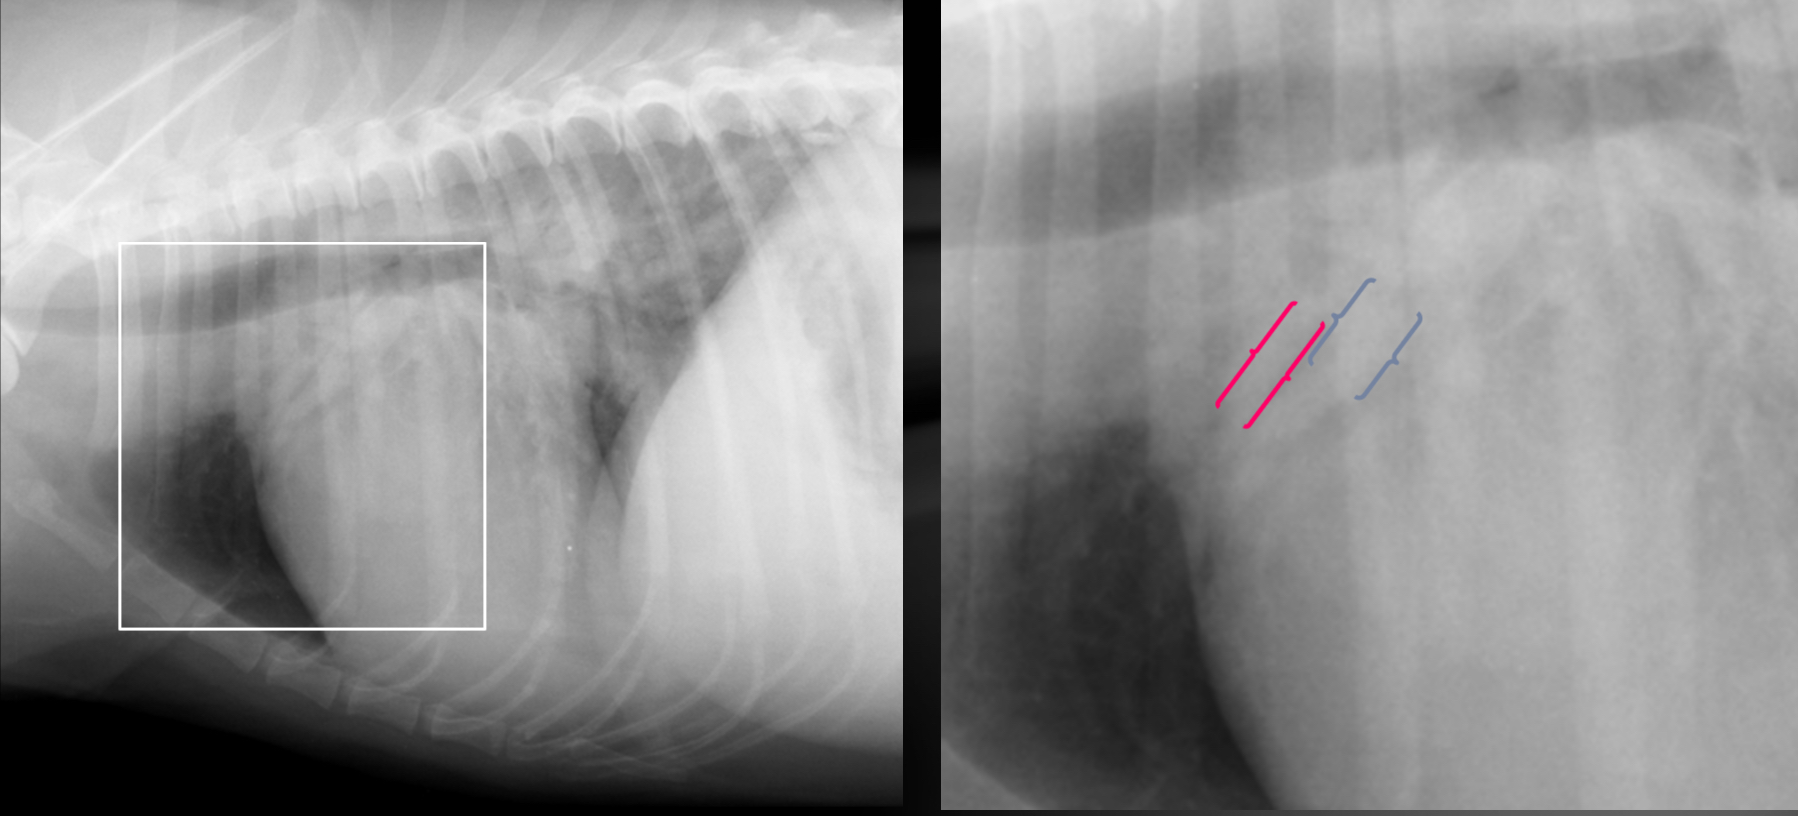

Cat - what sided HF is this

Dog - what sided heart failure is this

LHF

Cat- what sided heart failure

What features of this image screams this cat is in LHF

Pleural effusion

-scalloping and fissure lines present

-vessels are not traceable in cr.ventral thorax

Cat- what kind of heart failure is happening